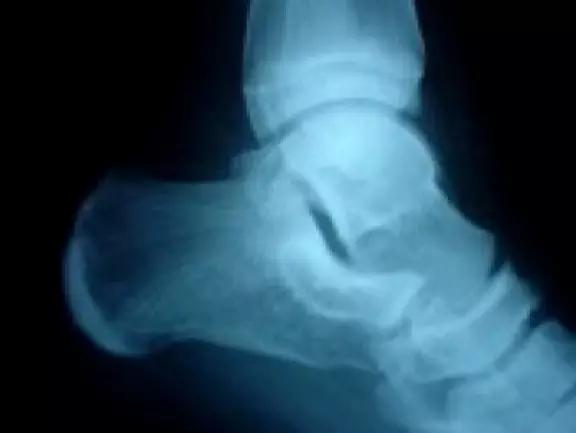

11. Shepherd 骨折

距骨后结节的骨折。

(来源:Talar process or tubercle [Shepherd’s fracture)